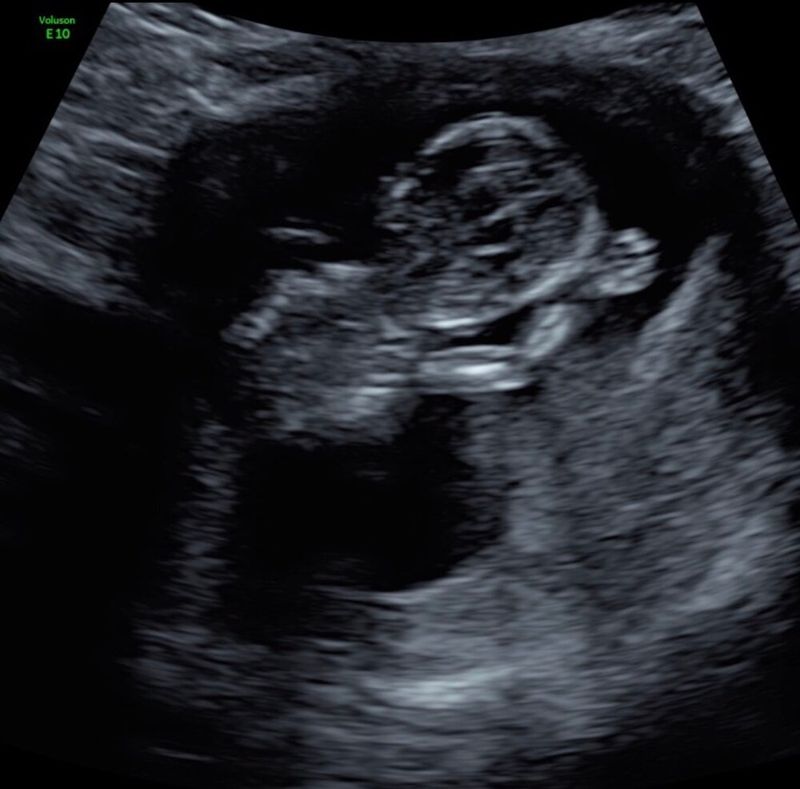

Jeje, finalmente el segundo trimestre y la ecografía de la fecha prevista. ¡Guau, este fue uno de los momentos más hermosos de mi vida! Un hermoso bebé saltando en mi vientre y ya tan completo. ¡Le agradecí a la ecografista con lágrimas en los ojos como 10 veces, a lo que ella respondió: 'Esto realmente lo han hecho ustedes mismos'. Alivio. Había sobrevivido la zona de peligro y mi embarazo ya no era un secreto. Las náuseas también podrían empezar a disminuir a partir de ahora, ¡aleluya! Pero a pesar de eso, no me sentía bien. Tenía poca energía y ganas para el día. 'Supongo que será por el dolor de pelvis y las náuseas, ¿verdad?'